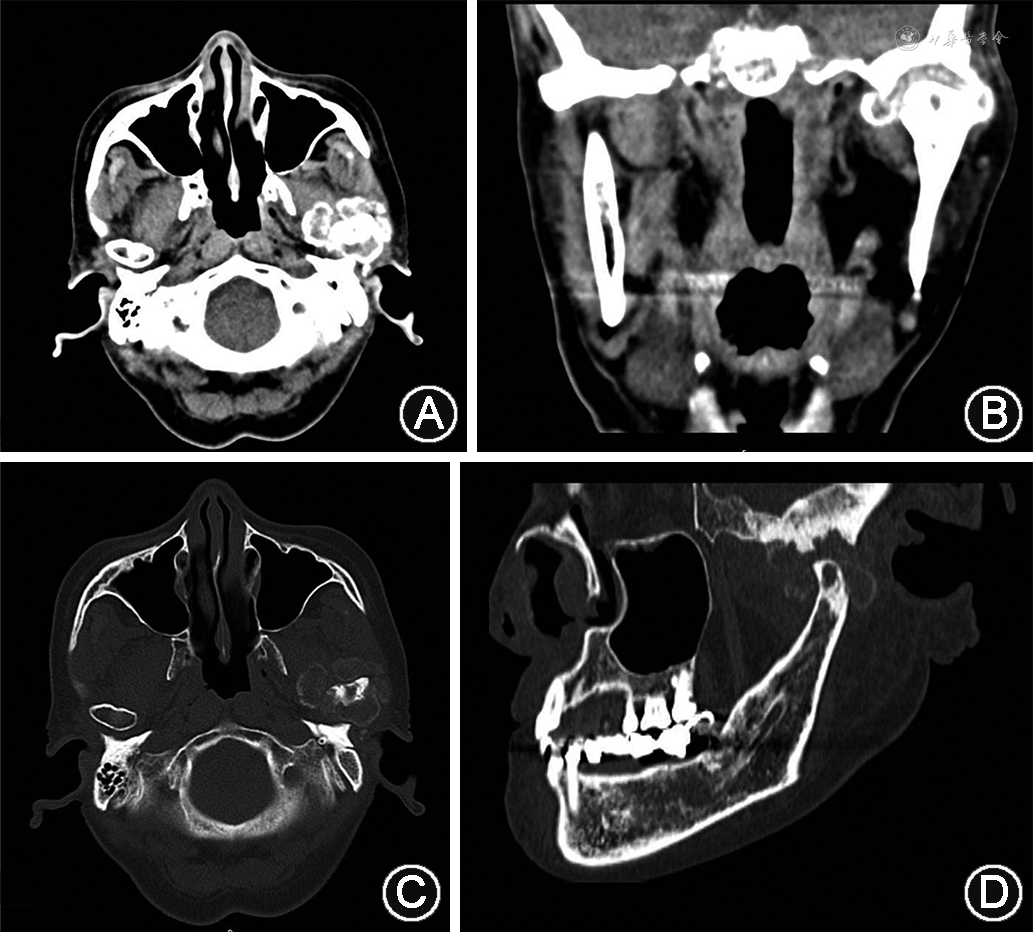

(2)影像学检查:见图1。螺旋CT提示左侧髁突膨大,骨质致密硬化,其内见不规则腔状吸收破坏,边缘不整。髁突周围团块状混杂密度影,周缘呈不规则环状、花边状高密度影。

(2)影像学检查:螺旋CT示右颞下颌关节外侧,右侧咬肌中后部至腮腺见不规则团状软组织块影,界限不清,边缘不规整,其内见大小不等斑片状絮状高密度影及钙化影,边缘毛躁。右下颌支和右颞下颌关节髁突未见明显异常骨质吸收或增生现象,骨皮质边缘光滑连续(图4B~D)。

TC的临床诊断主要依靠影像学,尤其是CT检查。CT可提供精确的位置、大小、与周围组织关系的信息,普通X线片通常只显示出与髁突相邻的大小不一的结节集聚而成的团块状钙化。在CT上,TC表现为关节旁或骨质邻近的软组织内菜花状、斑片状或结节状大小不等的圆形、长圆形或不规则的致密影,病灶内部及与周围组织间可有透明带分隔,可与骨组织相连,也可有邻近骨质受压吸收,病灶周围软组织受压改变[12]。与CT相比,MRI不常用,MRI通常在T2加权序列上显示非均匀的高信号强度,在T1加权序列上显示非均匀的低信号强度。另外,有研究报道,使用放射性标记的膦酸盐化合物锝[99TC]亚甲基二膦酸盐进行放射性核素扫描可用于诊断多发性病变、新形成的病变和监测病变活动[13]。